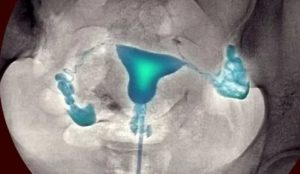

Вот так выглядит матка и маточные трубы после ввода контрастного вещества при гидросонографии.

Гидросонография – это метод диагностики, который позволяет оценить состояние маточных труб. В полость матки вводится контрастное вещество, а контроль его распределения осуществляется с помощью аппарата УЗИ.

По трубке в органы подается физиологический раствор. Врач с помощью специального датчика контролирует поведение маточных труб. Если они перекрыты спайками, то раствор по ним не пройдет.